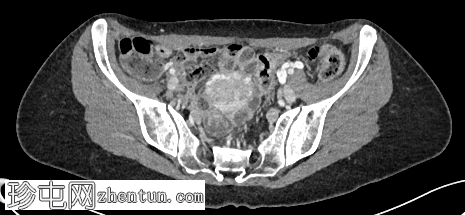

轴位增强扫描(门静脉期)

左肾肾盂肾盏系统及左侧输尿管,管壁环周增厚及强化,符合肾盂输尿管炎的影像学表现

左肾实质强化正常,无肾周脂肪浸润

膀胱充盈良好,无管壁增厚或周围脂肪浸润

无尿路结石

偶然发现肠系膜有一2.2 x 4 x 3.2 cm大小的边界清晰的均匀脂肪密度病变,符合肠系膜脂肪瘤的影像学表现

左侧卵巢静脉明显